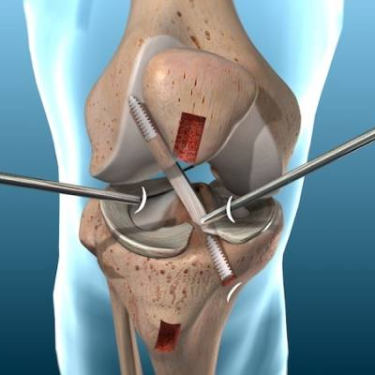

Expert surgical procedure to rebuild a torn anterior cruciate ligament (ACL) using advanced techniques.

Check Details